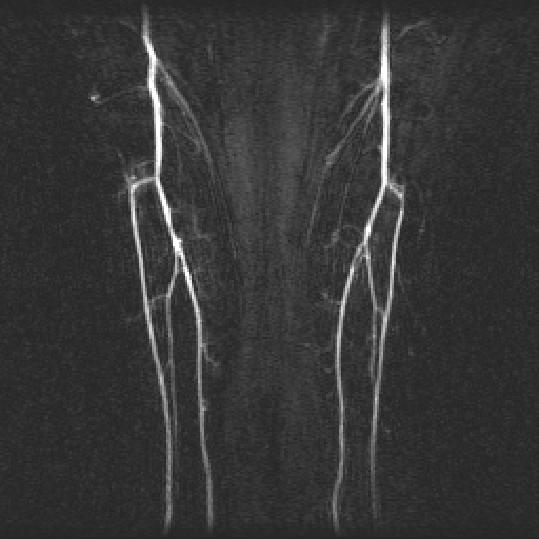

AutoDSA

ManualDSA

For time-resolved background-subtracted contrast-enhanced magnetic resonance angiography, the bright and sparse arterial signal allows unique identification of contrast bolus arrival in the arteries. This paper presents an automatic filtering algorithm using such arterial characterization for selecting arterial phase images and mask images to generate an optimal summary arteriogram. A paired double-blinded comparison demonstrated that this automatic algorithm is as effective as the manual process.